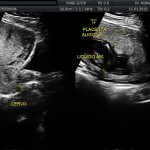

- El escenario Gravídico: Placenta, liquido, Cérvix y Anexos.